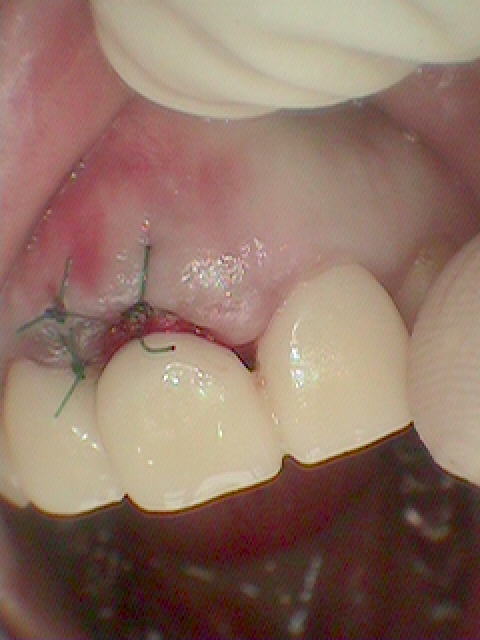

抜歯即時インプラント埋入を行っています

インプラント埋入後になります